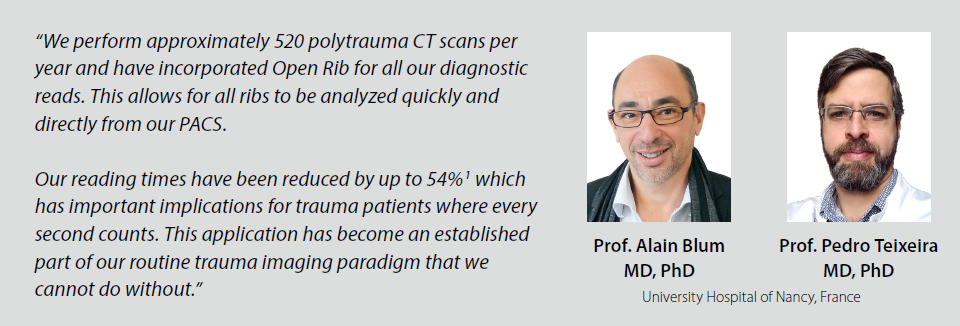

For trauma patients, every second counts

Open Rib: Opening New Insights in Thoracic Trauma Reporting